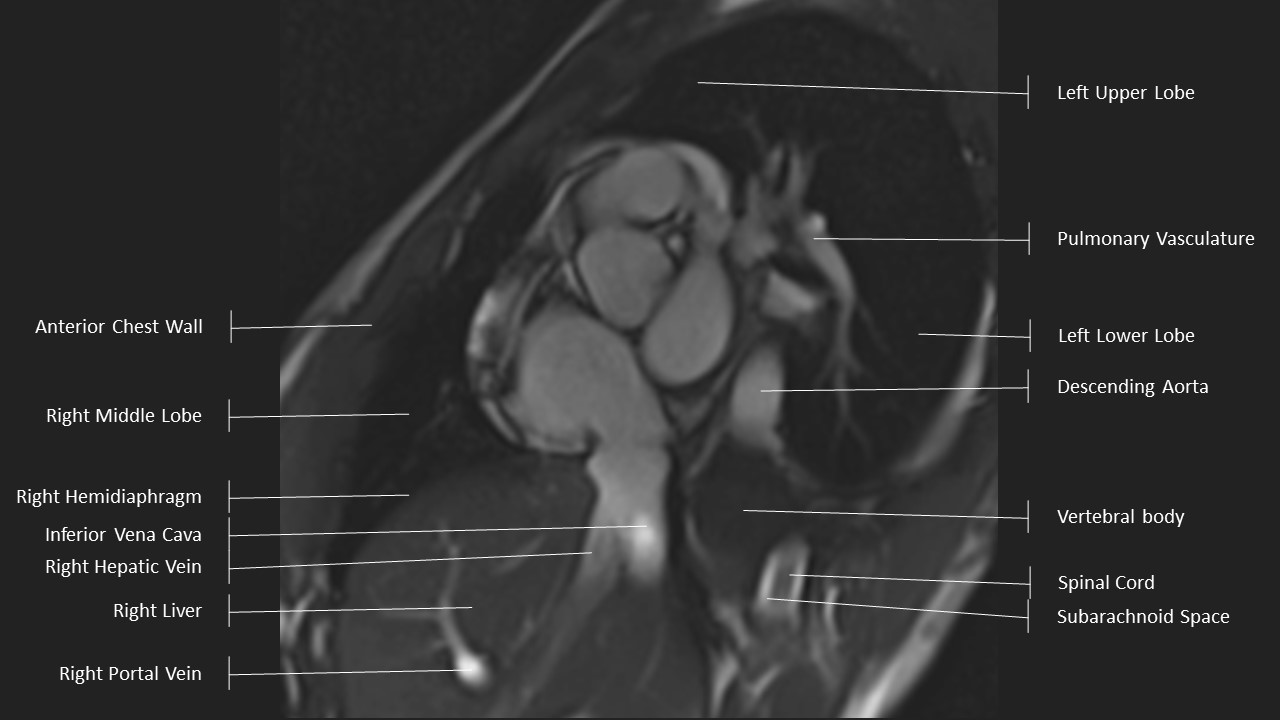

Short Axis Series